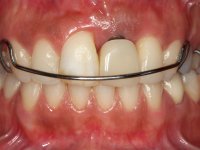

A paciente apresenta um desvio da linha média superior de 6 mm para a esquerda. Resultado da ausência do incisivo central superior esquerdo, os dentes adjacentes inclinaram mesialmente para esta zona, limitando o espaço disponível para a reabilitação prostodontica. Existe uma significativa desarmonia dentária negativa no arco maxilar como resultado da ausência do 21, ausência do primeiro pre-molar com um espaço residual, significativa redução coronária do segundo pre-molar direito, migração dos dentes posteriores para os espaços não preenchidos e uma mesialização molar superior esquerda e direita com uma relação molar em Classe II. Ambos os caninos esquerdo e direito mostram uma relação Classe II na posição de inter-cuspidação máxima. A paciente apresenta uma linha de sorriso média, um biótipo gengival médio grosso, apresenta uma correcta higiene oral sem doença periodontal. Não apresenta hábitos para –funcionais. O exame radiográfico mostra uma significativa inclinação dos eixos dos dentes 11 e 22 com espaço entre a porção apical das raízes. A análise cefalométrica foi feita com o intuito de explorar a hipótese de conseguir arranjar espaço para a colocação de um implante e de uma coroa no local do dente 21. Finalmente a morfologia do osso residual presente na região anterior da maxila foi avaliado com uma TAC, revelando uma perda das dimensões da parede óssea vestibular.

2) Tratamento ortodôntico com o objectivo de criar espaço entre as raízes e as coroas dos dentes 11 e 22,